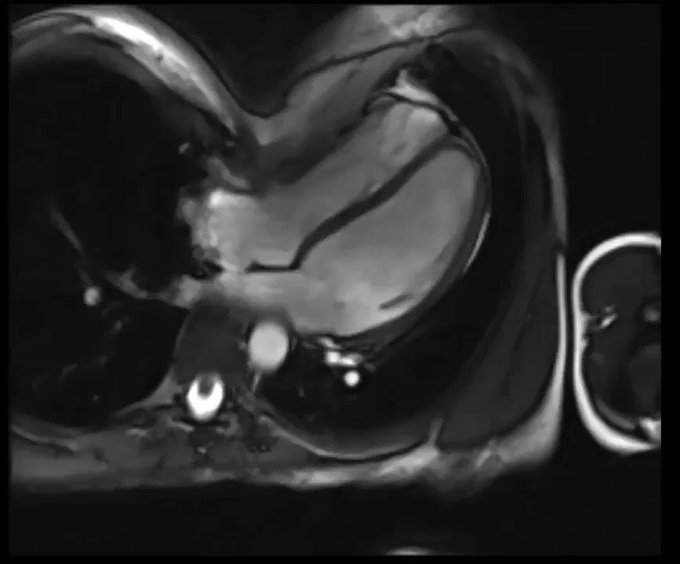

Pectus Excavatum and RV Compression in a Young Athlete with Syncope on #CardiacMRI via @mvaduganathan

Search "Pectus Excavatum" to find and bookmark this image on GrepMed -> https://t.co/M3SLRPEgeK

#FOAMed #Meded #Cardiotwitter